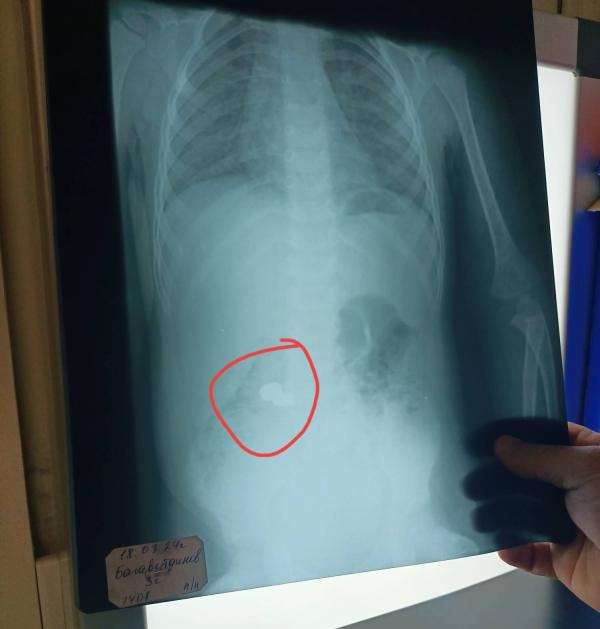

Спасибо всем кто меня до усрачки напугал это был хороший пинок чтоб я не сомневалась ехать среди ночи в другой конец города одна с ребёнком на такси или нет 🥹🥹🥹❤️❤️❤️

Поехала сделали снимок и Альхамдулилля смогли сразу вытащить.

Врач сказал молодцы что сразу приехали а я подумала как хорошо что есть эта прога и девочки которые всегда посоветуют что делать 🫶🏻🫶🏻🫶🏻🫶🏻

С момента как он проглатил эти батарейки пока вы...